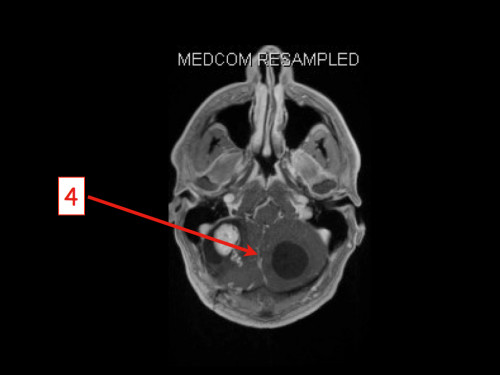

3. Schwindel und Kopfschmerzen, 3 Jahre nach Phäochromozytom-Resektion

Schwindel und Kopfschmerzen, 3 Jahre nach Phäochromozytom-Resektion

19-jähriger Mann. Er klagt seit mehreren Wochen über Schwindel und Kopfschmerzen. Im Alter von 16 Jahren sind er und sein Zwillingsbruder an einem Phäochromozytom operiert worden.